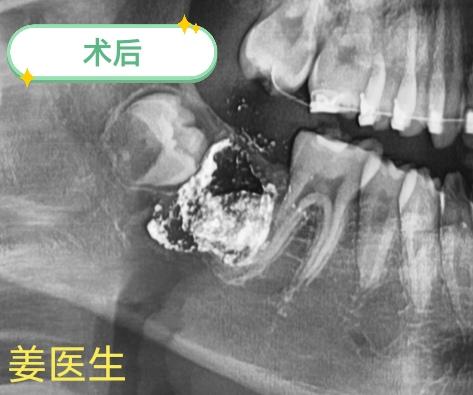

正畸转诊,拔除骨埋伏47。

口腔姜健